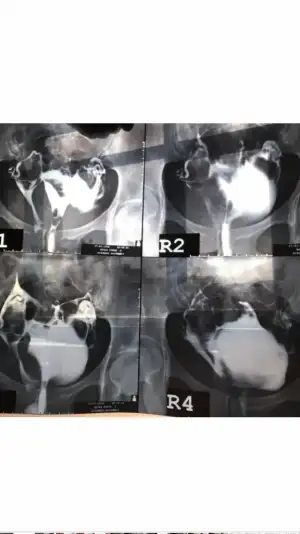

Rahimde anormallik teşhisi kondu.bikornis(çift boynuz) ve Septum (perde)diyenler oldu.3 kimyasal gebeliğim var.kafam karışık acaba hangisi?perde ise ameliyatı var bikornis ise ameliyatı yok diyorlar.yardımcı olur musunuz lütfen?

Perde mi çift boynuz rahim mi